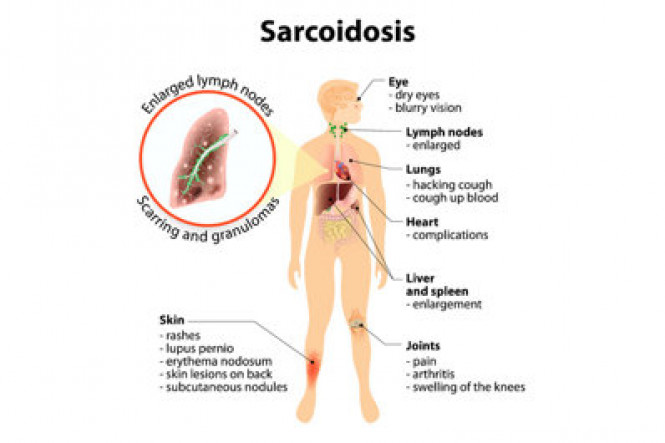

Respiratory diseases

Respiratory diseases are conditions that affect any of the processes involved with breathing. If you or someone you know are one of the 1 in 6 New Zealanders that lives with a respiratory condition, here you can find some useful information on how to manage the condition well.